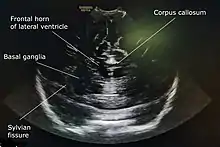

Technique

A 5 to 7.5 MHz probe is used to scan deeper structures in the brain. A 7 to 12 Mhz probe is used for scanning superficial structures for detecting lesions between the brain and the skull, superior sagittal sinus thrombosis, cerebral oedema, and evaluating the structures of sulci and gyri.[4]

A water-based gel is applied to the infant's head, over the anterior fontanelle, to aid conduction of ultrasound waves. Ideally scans are performed during sleep or when the infant is calm. The operator then uses an ultrasound probe to examine the baby's brain, viewing the images on a computer screen and recording them as necessary.

A standard cranial ultrasound examination usually involves recording of approximately 11 views of the brain from different angles, six in the coronal plane and five in the sagittal and parasaggital planes.[7] This allows all parts of the ventricles and most of the rest of the brain to be visualised.